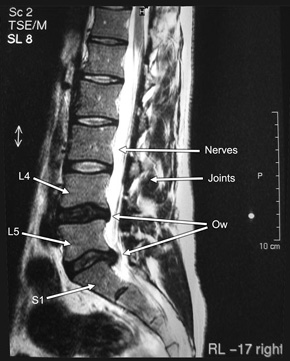

On October 4, 2003 I saw Dr Crisp again, at 8am (ugh). He showed me several slices through my body; the one I’ve included here on the right highlighted the problem most clearly. It was just as expected.

At L4/5 the disc is dehydrated with a minimal non-compressive midline protrusion.

At L5/S1 the disc is dehydrated and slightly reduced in height. There is a small focal herniation in the midline which narrows the right lateral angle displacing and mildly compressing the S1 nerve root. The thecal sac and neural foramina are not compromised.

The remaining lumbar discs are normal. The distal cord and conus are normal.

In plain English: the creamy caramel inside two of my discs had oozed out of the crispy shell, and in one case (the disc between L5 and S1) was squashed up against a nerve. Result: pain.